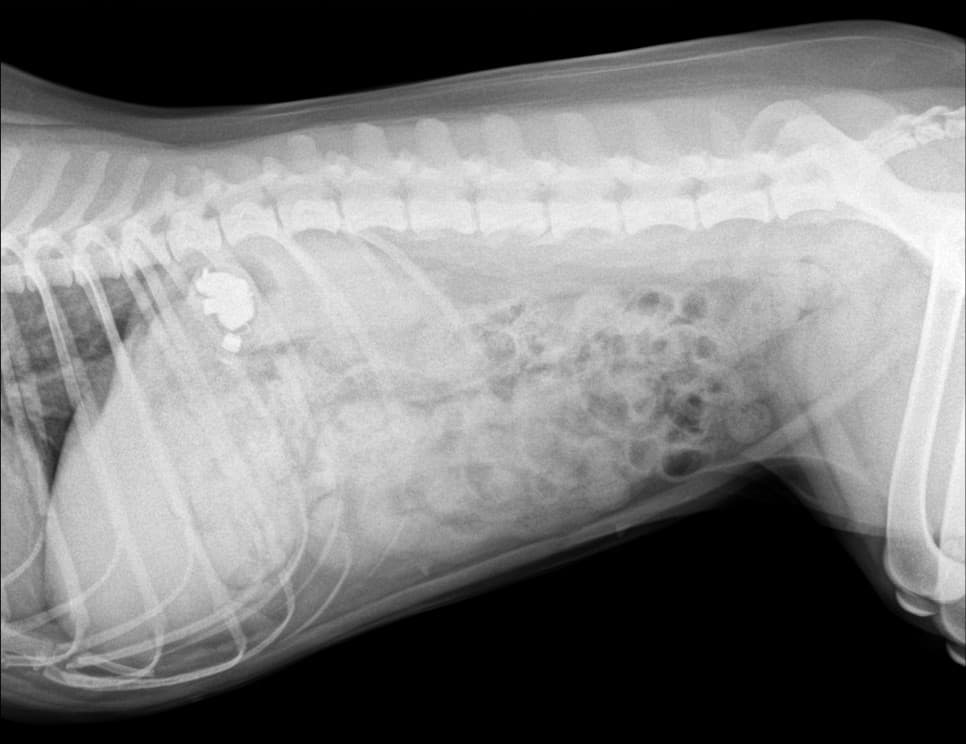

위에 금속성의 이물질이 발견 되었는데요 바로 무선 이어폰 에어팟 프로 이었습니다.

이물 제거는 개복을 통한 수술 방법도 있지만 비침습적인 내시경을 통해 제거가 가능 합니다.